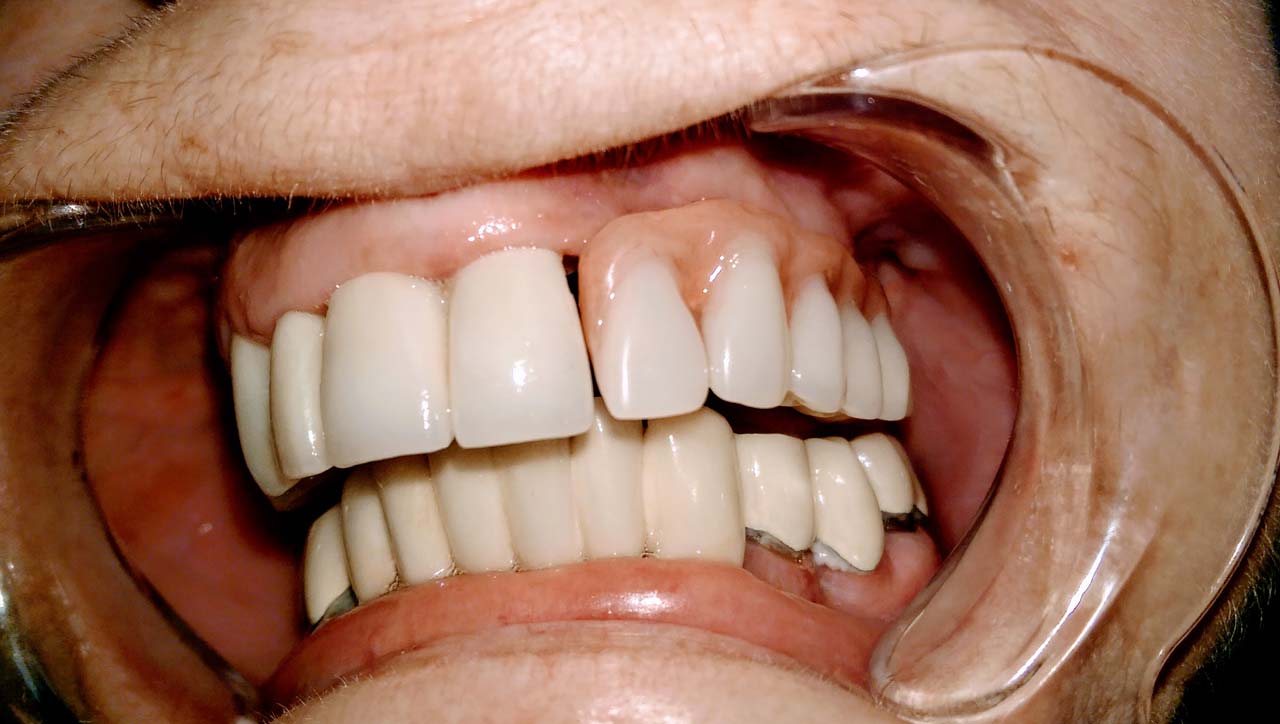

Teljes szájüregi rehabilitáció két lépésben

Ismét egy teljes szájüregi rehabilitáció két lépésben. Először az alsó fogak lettek kihúzva és azonnal implantálva, híddal ellátva, majd később a felső. IHDE svájci azonnal terhelhető implantátumok és cirkónium hidak. Dr. Kelemen Péter és a Symbion Fogtechnika közös munkája.